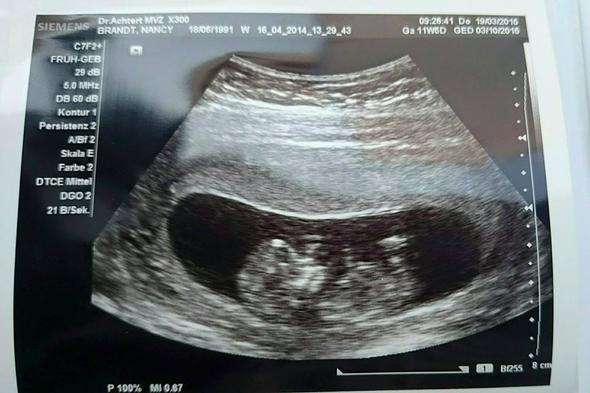

13 SSW Ultraschall Das ist zu sehen Das kleine Wesen wiegt zwischen 14 und 18 Gramm in der 13 SSW Seine Größe beträgt jetzt ungefähr sechs Zentimeter Man kann im Ultraschallbild in der 13 SSW die Rippen, Bein und Beckenknochen erkennen Auch schlucken kann ein Baby in der 13. Frage Guten Dr Bluni, Ich war bei 130 beim Arzt zum großen Ultraschall (Ersttrimesterscreening) und auf meine Frage hin, schaute die Ärztin auch nach dem Geschlecht Das Baby hat sich sehr stark bewegt und nicht wirklich was gezeigt Natürlich ist es auch noch sehr früh, die Ärztin meinte aber trotzdem, dass sie zwischen den Beinen etwas sehen würde und demnach würde sie sagen. 1 Dein Körper in der 13 SSW Mit der 13 SSW und dem Start in das 2 Trimester beginnt die schönste Zeit der Schwangerschaft, da die ersten Beschwerden nachlassen und der Bauch langsam sichtbar wird Außerdem.

Mit der 13SSW beginnt das zweite Trimester der Schwangerschaft, nämlich der vierte SchwangerschaftsmonatDieser Schwangerschaftsmonat wird von vielen Schwangeren als Erholungs und Entspannungsphase betrachtet, da die Anzeichen und Symptome der Schwangerschaft (zB Übelkeit, Unterleibsschmerzen, Bauchschmerzen) zürckgehen und das Baby nur noch wächst, was im Ultraschall besonders. 13 SSW Ultraschall Deines Babys in der 13 Schwangerschaftswoche In der 13 SSW ist Deine Gebärmutter so groß wie eine Faust Dein Baby ahmt in der 13 SSW schon das Atmen nach und dehnt so sein Zwerchfell Die Stimmbänder im Kehlkopf Deines sechs Zentimeter großen und 14 Gramm schweren Babys entwickeln sich auch schon. 1 Dein Körper in der 13 SSW Mit der 13 SSW und dem Start in das 2 Trimester beginnt die schönste Zeit der Schwangerschaft, da die ersten Beschwerden nachlassen und der Bauch langsam sichtbar wird Außerdem.

Präeklampsie Screening zeitgleich mit dem Combined Test Aufgrund wissenschaftlicher Daten der letzten Jahre, empfehlen wir eindringlich den Combined Test mit einem Screening für Präeklampsie (lt Volksmund Schwangerschaftsvergiftung) zu kombinieren Die alte Bezeichnung Schwangerschaftsvergiftung ist zum Teil irreführend Es handelt sich hier um eine Schwangerschaftskomplikation im. SSW sind Sie 12 Wochen und x e schwanger – die 13 SSW besteht demnach aus den en 1 = Im Ultraschall sind die Knochen von Armen und Beinen, aber auch die Wirbelsäule, die Rippen und die Schädelknochen nun gut zu erkennen Der Schädel des Fötus besteht aus großen und gewölbten Knochen. Hatte heute meinen FATermin!.